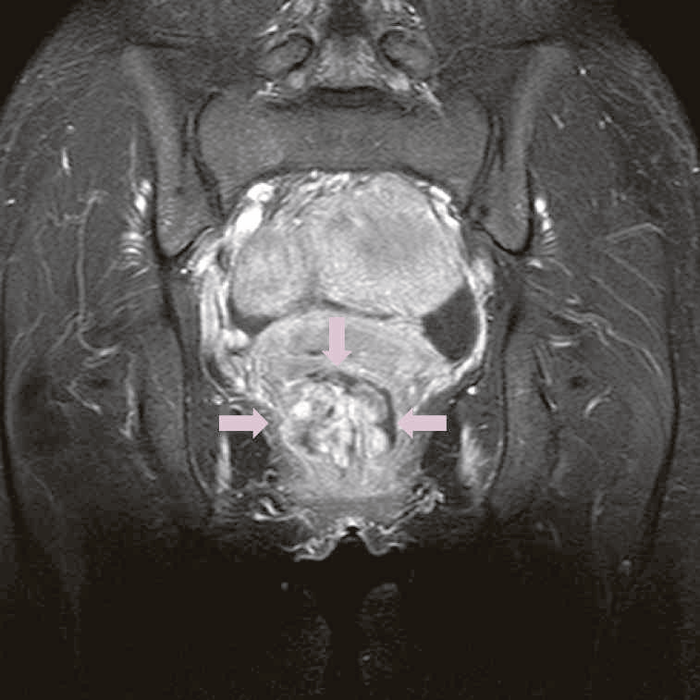

症例3 直腸肛門管癌(60歳代男性)

精査で施行したCT,MRIで痔瘻癌が疑われた。

診断時のMRIでは直腸下部壁内から周囲にhigh intensity areaが拡がり,右側には痔瘻の瘻管を認めた。high intensity areaは前方で前立腺や陰茎海綿体付近まで広がっていた。

CTではMRIと同様に広範囲のhigh density areaがあり,癌と炎症が波及した領域の区別がつかず右側方領域にリンパ節腫大を認めた。